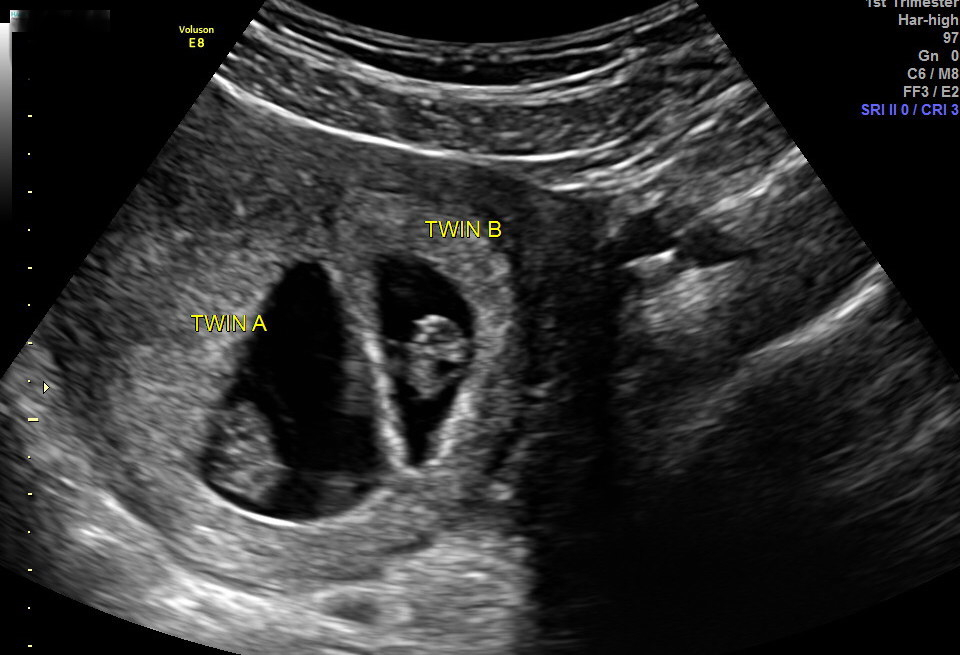

My 8 week ultrasound pic from last week - my husband and I found out we’re having twins! Di dizygotic twins, so they will most likely be fraternal but if they are the same sex we won’t know for sure if they are identical until they are born. Right now they are both looking healthy and have strong little heartbeats of 155 and 169 bpm. Can’t wait to continue watching them grow!